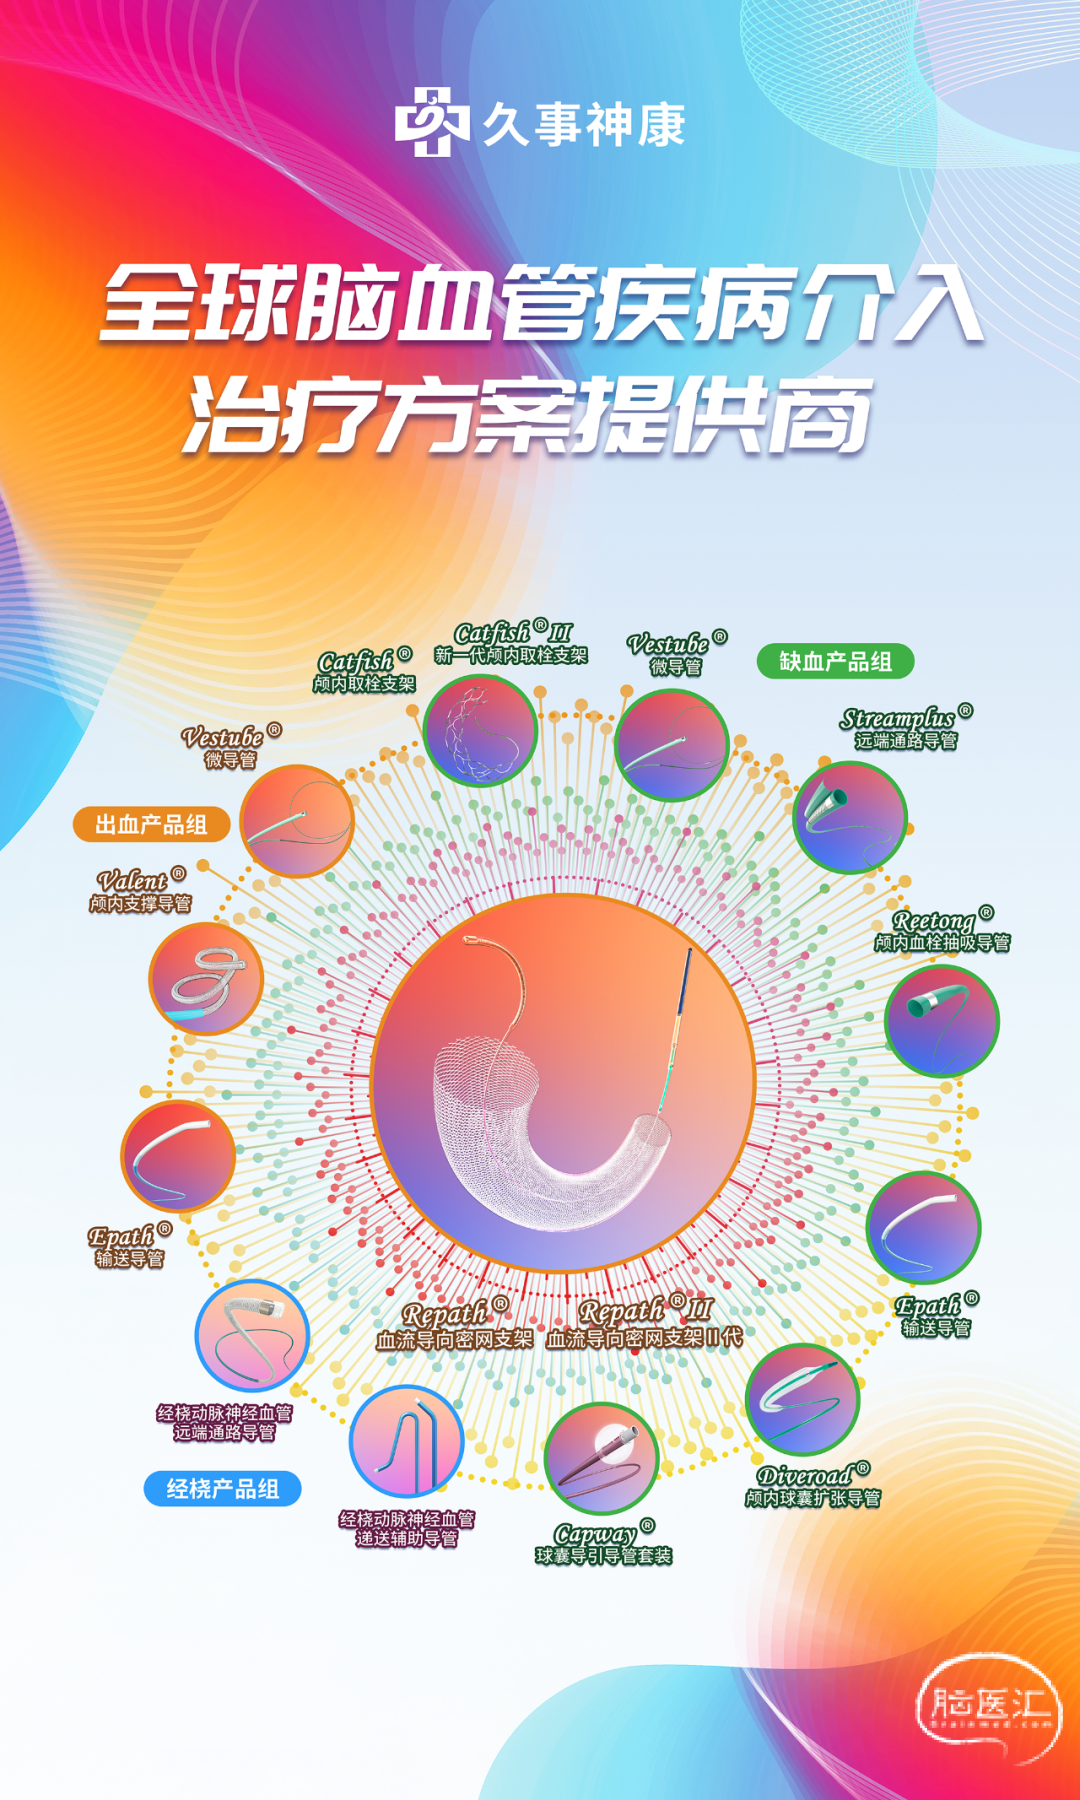

久事神康

北京久事神康医疗科技有限公司成立于2016年8月,是一家专注于三类植介入医疗器械研发、生产、销售的公司,公司始终秉承“诚信、创新、卓越、高效”的精神,创新研发临床应用前沿的颅内血管介入和植入医疗器械,满足中国临床需求;传承大国工匠精神,打造高端植介入颅内医疗器械民族品牌。